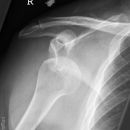

Schulterluxation